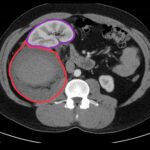

The authors present the case of a 42-year-old male who was evaluated in a community hospital emergency department (ED) with right upper quadrant and flank pain after falling onto his couch. His evaluation included computed tomography (CT) of his abdomen with intravenous contrast that identified a large right retroperitoneal hematoma measuring an impressive 17 centimeters (cm) in length. The patient was transferred to a receiving trauma center. Upon arrival a focused assessment with sonography in trauma (FAST) ultrasound was obtained. The interpretation of the findings was complicated by distortion of his anatomy by the hematoma. The patient remained hemodynamically stable and was admitted for continued observation. He was ultimately discharged home in stable condition. This case report provides a concise overview of the approach to evaluating blunt abdominal trauma, imaging considerations, and a brief review of the management of retroperitoneal hematomas.